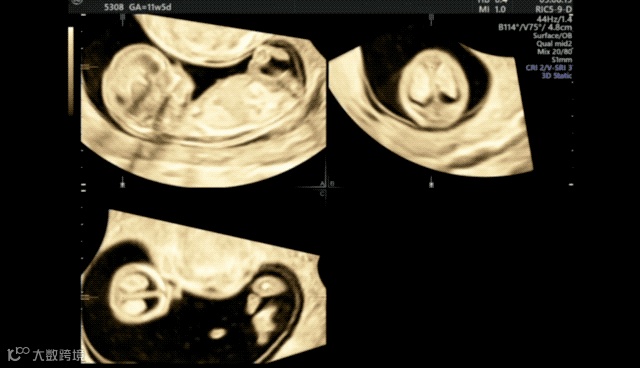

在超声机菜单上选取muti-plane、四幅画面,获得这张图。muti-plane多平面模式不同于render渲染模式,渲染模式下选择单幅画面只会显示3维图像,多平面模式就可以单独放大abc平面。

A平面是胎儿矢状切面,B平面是胎儿横切面,c平面是胎儿冠状切面。单纯旋转a切面很难获取标准正中矢状切面的,我们需要借助bc平面,只要bc平面标准了,a平面也自然是标准了。所以bc平面要选择能够快速识别是否标准的标志物,这里我选择了大脑镰,目标是b平面上大脑镰绝对垂直、c平面上大脑镰绝对平行,这样我们的a平面就是胎儿正中矢状切面了